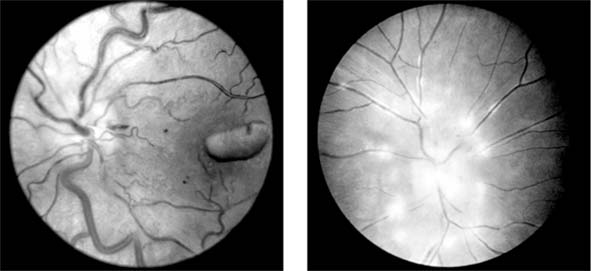

The appearance of the fundus in hypertensive retinopathy is determined by the degree of elevation of the blood pressure and the state of the retinal arterioles. Thus, in young patients with accelerated hypertension, an extensive retinopathy is seen, with hemorrhages, retinal infarcts (cotton-wool spots), choroidal infarcts (Elschnig's spots), and occasionally serous detachment of the retina (Figure 15-10). Severe disk edema is a prominent feature. Vision may be impaired but is restored if blood pressure is reduced with caution.

Figure 15-10

Figure 15-10: Accelerated hypertension. Fluorescein angiogram in a young man showing arteriolar constriction, dilation of capillaries with microaneurysms, and areas of closure. Marked disk edema is present.

In contrast, elderly patients with arteriosclerotic vessels are unable to respond in this manner, and their vessels are thus protected by the arteriosclerosis. It is for this reason that elderly patients seldom exhibit florid hypertensive retinopathy (Figure 15-11).

Figure 15-11

Figure 15-11: Accelerated hypertension. Fluorescein angiogram in an elderly wom.an showing marked arteriolar constriction and irregularity but few signs of florid retinopathy.

Fluorescein angiography has made possible accurate documentation of these microcirculatory changes. In young patients with hypertension, arteriolar attenuation and occlusion are seen, and capillary nonperfusion can be verified in relation to a cotton-wool spot, which is surrounded by abnormal dilated capillaries and microaneurysms with increased permeability on fluorescein angiography.

Resolution of the cotton-wool spots and the arteriolar changes occurs with successful hypotensive therapy. In elderly patients, the underlying arteriosclerotic changes are irreversible.